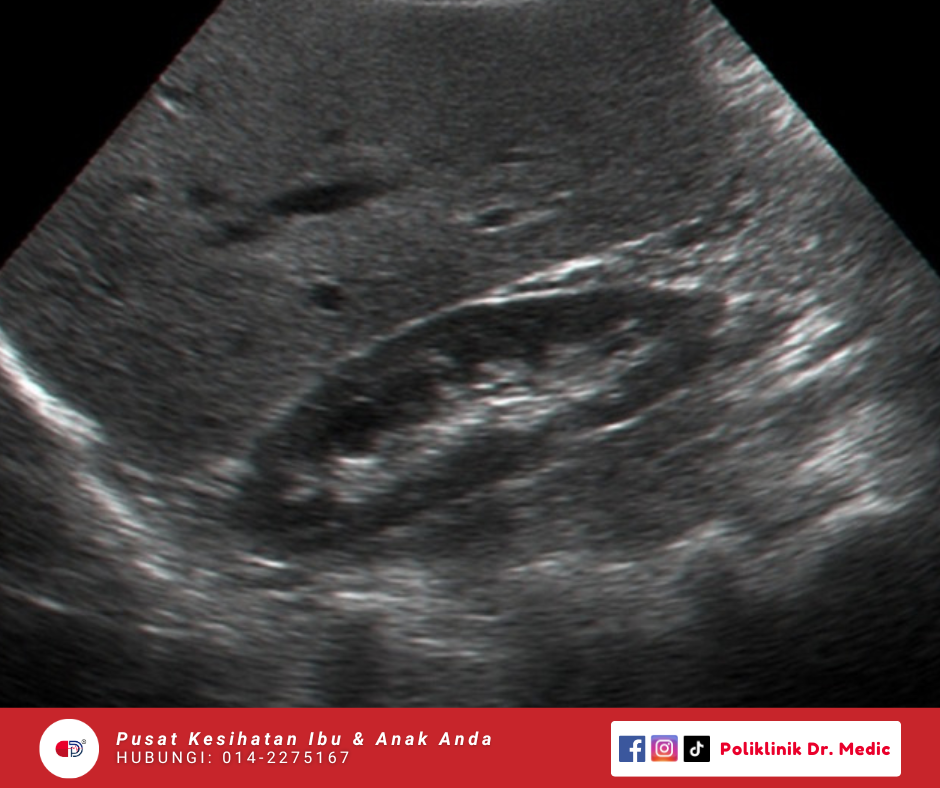

Transvaginal Scan

Imbasan dalaman guna probe kecil melalui faraj untuk lihat rahim, ovari, dan kawasan sekeliling dengan lebih jelas. Biasanya dibuat untuk kes macam period tak teratur, cyst, pendarahan luar biasa, atau masalah kesuburan.

RM60